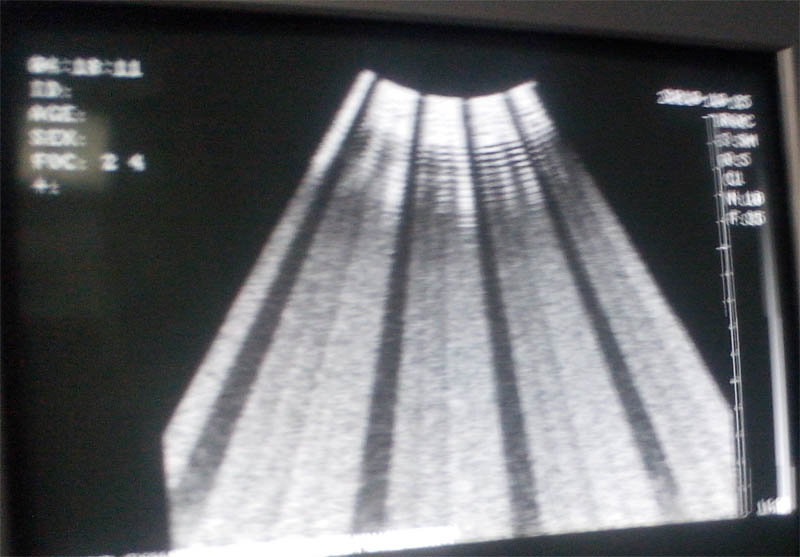

国产杂牌B超有暗道

暗条从上到下都是通的。其他图像及回声正常